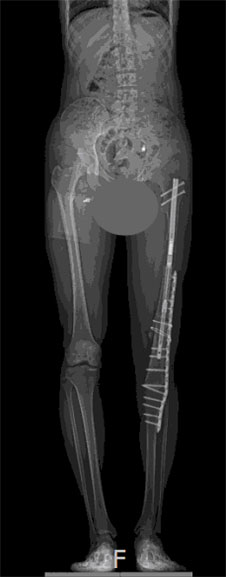

사지연장술은 한쪽 다리가 짧은 하지부동 환자뿐 아니라, 왜소증 환자에게도 필요한 수술이다./사진=이동훈연세정형외과 제공

사지연장술은 한쪽 다리가 짧은 하지부동 환자뿐 아니라, 왜소증 환자에게도 필요한 수술이다. 최근에는 작은 키로 인해 심각한 콤플렉스가 있는 분들에게 일명 '키 크는 수술'로 시행되기도 한다. A씨가 선택한 연장 방법은 프리사이스(PRECICE)라는 내고정 연장 방식으로, 기존의 외고정 장치가 가지고 있던 통증, 핀 감염, 심한 흉터 등의 합병증을 피할 수 있는 수술 방법이다. 네일 안의 자기장을 이용해 외부에서 ERC로 자동 연장할 수 있다. 이 장치는 수술 후 약 2년 후에 제거한다.